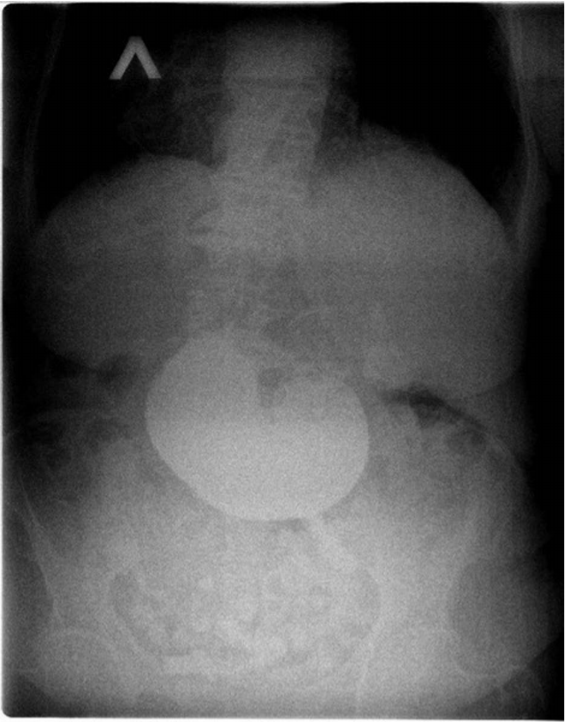

1. Больная З., 77 лет (1945 г.р.), поступила в приемно-диагностическое отделение Клиники БГМУ на 9-е сутки от начала заболевания с жалобами на интенсивные боли в животе, рвоту, тошноту и общую слабость. Из анамнеза: в течение 5 лет отмечает периодические приступы болей в правом подреберье, связанные с нарушением диеты. За медицинской помощью с данными жалобами не обращалась, самостоятельно принимала спазмолитики. Объективно: общее состояние средней степени тяжести, стабильное. Кожные покровы бледно-розовой окраски, чистые, сухие. Дыхание везикулярное во всех отделах, хрипов нет. АД 135/80, ЧСС 87 в мин. Язык сухой, обложен белым налетом. Живот подвздут, мягкий, болезненный в правом подреберье и эпигастрии. Перитонеальные и аппендикулярные знаки отрицательные. Перистальтика выслушивается вялая. Физиологические отправления не нарушены. При ректальном осмотре тонус сфинктера удовлетворительный, опухолевидных образований в ампуле прямой кишки не выявлено, на перчатке следы кала обычного цвета. Результаты общего анализа крови: лейкоциты — 17,1×10 9 /л, эритроциты — 6,7×10 12 /л, гемоглобин — 168 г/л. По данным биохимических исследований крови: общий белок — 67 г/л, общий билирубин — 17,6 мкмоль/л, прямой билирубин — 10,3 мкмоль/л, глюкоза — 15 ммоль/л, мочевина — 9,2 ммоль/л, амилаза крови — 25 ед/л, креатинин — 130 мкм/л. По ультразвуковому исследованию (УЗИ) брюшной полости желчный пузырь сокращен, в просвете конкременты до 10 мм с эхотенью, холедох не расширен — 7 мм, просвет его свободен. В брюшной полости повышенная пневматизация кишечника, определяется вялая перистальтика. Свободная жидкость в брюшной полости и малом тазу не визуализируется. Пациентке был дан барий. По данным обзорной рентгенографии брюшной полости имеются признаки дуоденальной непроходимости (уровень контрастного вещества в желудке) (рис. 1).

![]()

Рисунок 1. Рентгеновский снимок дуоденальной непроходимости

Figure 1. Duodenal obstruction X-rayПосле в инфузионно-спазмолитической терапии выполнена фиброгастродуоденоскопия, на которой визуализируются до 500 мл застойной жидкости в желудке с остатками пищи, множественные острые эрозии в желудке. Луковица двенадцатиперстной кишки обтурирована, предположительно безоаром. На стенках двенадцатиперстной кишки множественные пролежни в виде язв глубоких размеров различной формы и величины. Со стороны передней стенки — участок, подозрительный на перфорацию. С учетом полученных данных установлен предварительный диагноз: Острая обтурационная дуоденальная непроходимость, что явилось показанием к экстренному оперативному вмешательству. Проведена предоперационная подготовка, осмотр анестезиолога и терапевта, и пациентка доставлена в операционную.